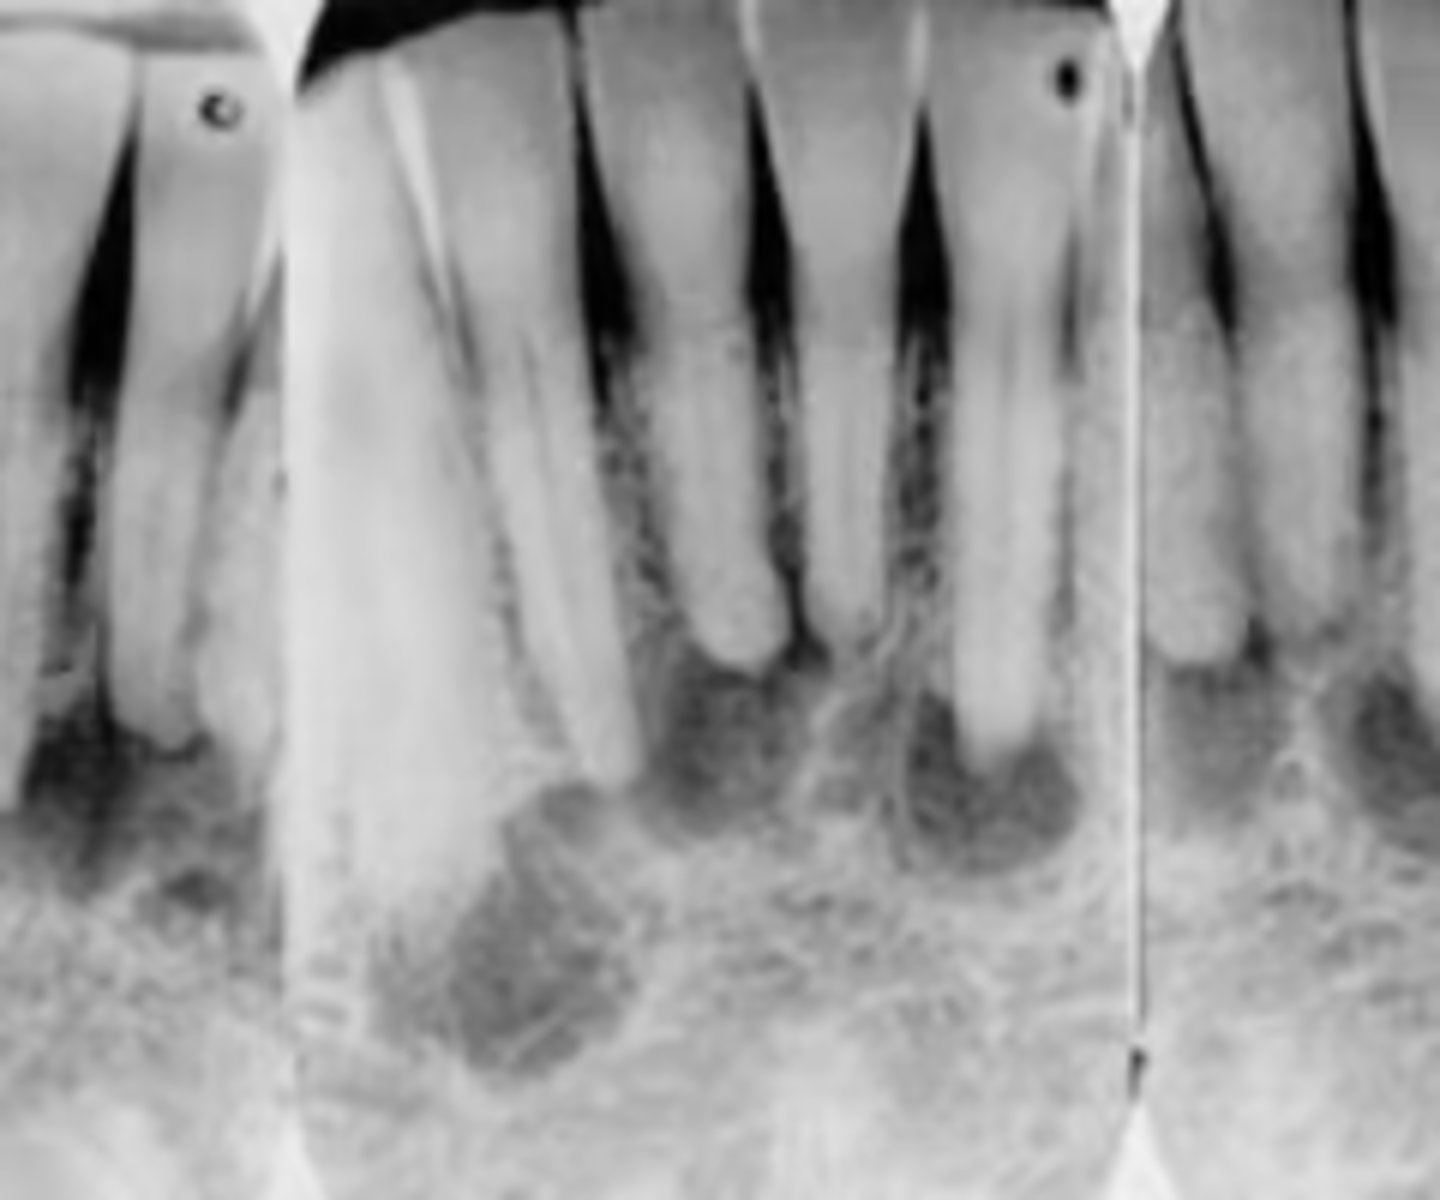

how would you describe this lesion?

A. well-defined, periapical radiolucent lesion associated with #24 and 25

B. ill-defined, periapical radiolucent lesion associated with #24 and 25

C. well- defined, multilocular periapical lesion associated with tooth number 24 and 25

D. mixed density, periapical lesion associated with teeth number 24 and 25

- Also note loss of apical lamina dura of 24, 25

What category would this lesion be part of?

Dysplasia

What would be a differential diagnosis for this lesion?

PCOD (stage 1)